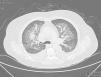

Hemorragia alveolar difusa asociada a púrpura de Schönlein-Henoch e infección por Pneumocistis jirovecci: a propósito de un caso

Diffuse alveolar hemorrhage associated with Henoch-Schönlein purpura and Pneumocystis jirovecii infection: A case report